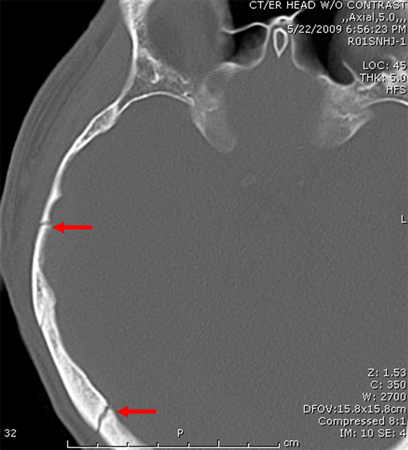

A history of head trauma (to detect intracranial bleeding or haematoma)

[Figure caption and citation for the preceding image starts]: Occipital fracture extending to foramen magnum: risk of brainstem compression by haematoma.From the teaching collection of Demetrios Demetriades, Division of Trauma and Surgical Intensive Care, LAC/USC Trauma Center, Keck School of Medicine at USC; used with permission [Citation ends].

[Figure caption and citation for the preceding image starts]: Linear parietal fracture without depressionFrom the teaching collection of Demetrios Demetriades, Division of Trauma and Surgical Intensive Care, LAC/USC Trauma Center, Keck School of Medicine at USC; used with permission [Citation ends].

[Figure caption and citation for the preceding image starts]: Fracture of temporal bone.From the teaching collection of Demetrios Demetriades, Division of Trauma and Surgical Intensive Care, LAC/USC Trauma Center, Keck School of Medicine at USC; used with permission [Citation ends].